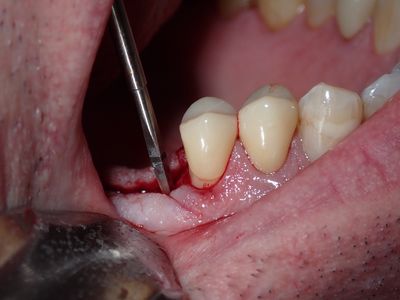

straightforward implant placement with densah drills used at apical end. no entry into sinus chamber, dense bone, had talked about doing a sinus lift but is best to reduce length of procedure.